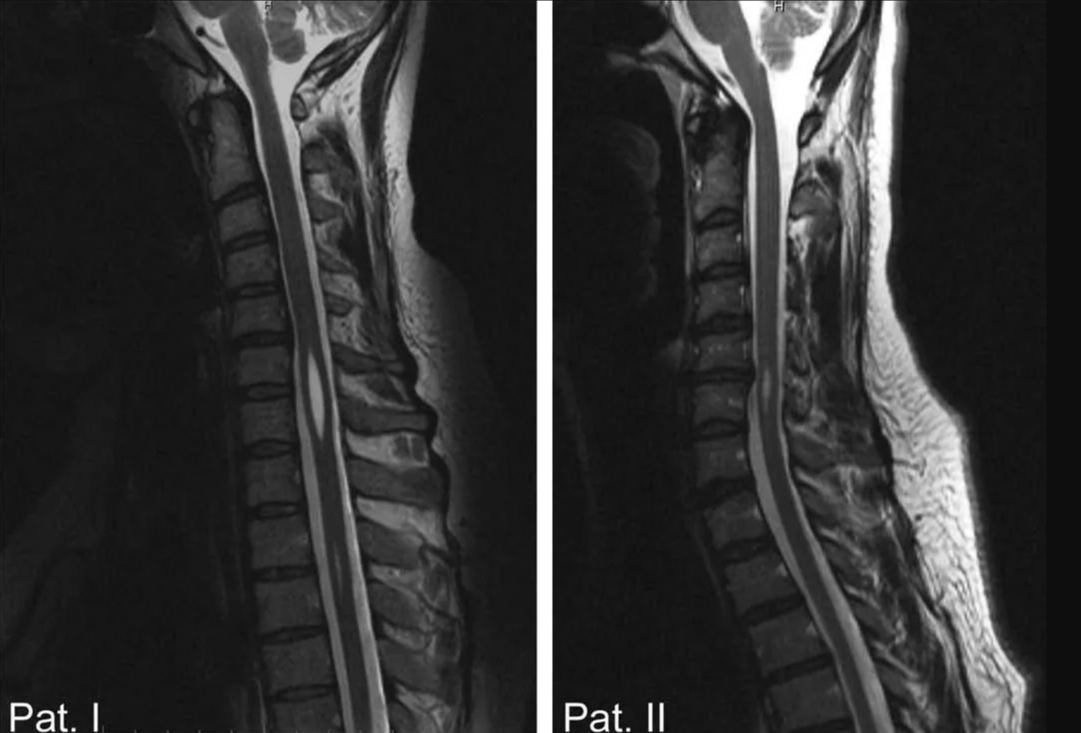

Гидромиелия спинного мозга клинический случай.

После проведенного осмотра принято решение о проведении МРТ головного мозга, МРТ шейного и грудного отдела позвоночника.

Q06.4 – Гидромиелия шейного и грудного отдела спинного мозга.

Гидромиелия - представляет собой расширение центрального канала спинного мозга.

При помощи МРТ можно обнаружить точное положение гидромиелических полостей и их размер.